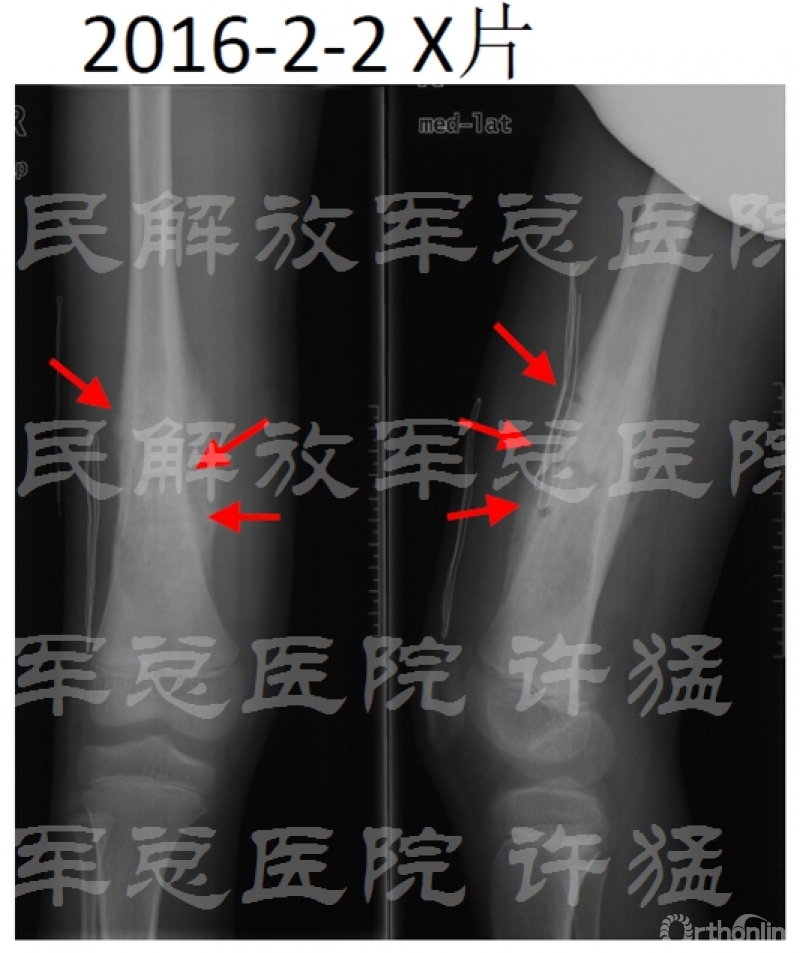

术后随访: